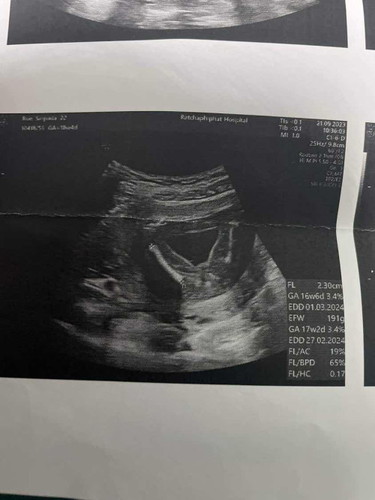

สอบถามค่ะเพศน้อง หญิงหรือชาย

หมอไม่ได้บอกอะไรเลยค่ะ อยากทราบมากๆแม่ๆช่วยดูหน่อยนะคะ

เราว่าผู้หญิงค่ะ ไม่มีจู๋ออก

หญิงหรือชายค่ะแม่ๆใครดูออก

น่าจะ ผญ ถ้า ผช จู๋โผล่แล้ว

ผู้หญิงคะ

หญิงค่ะ

หญิงคะ

ชายค่ะ